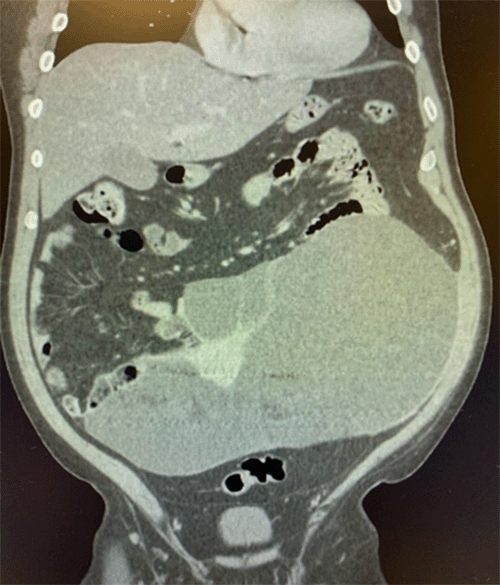

Physical examination revealed a distended abdomen with focal tenderness in the left lower quadrant and hypogastric region. A soft mass was readily palpable in this area. Abdominopelvic CT scan identified a large (30 × 14 × 17 cm) cystic mass with areas of calcification arising from either the mesentery and/or the distal small bowel (Figure 1).

Figure 1. Abdominopelvic CT Scan of Giant Cystic Mass. Published with Permission